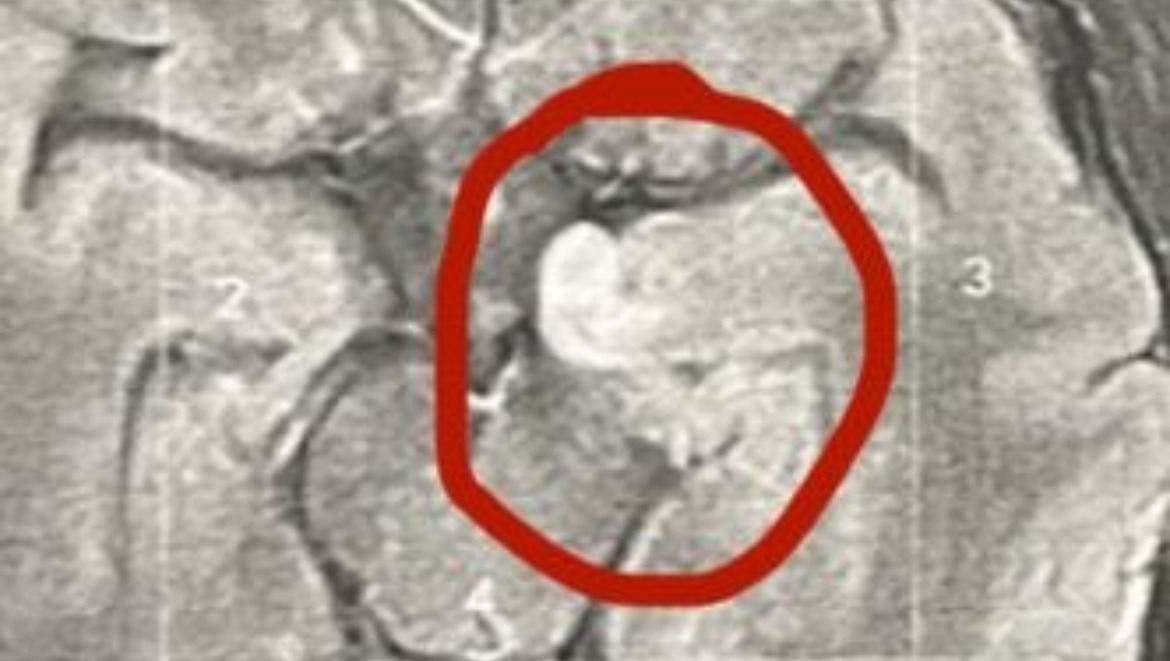

The tumour is located is in his Front Left Temporal lobe and it is effecting his Memory, Speech, Emotions and also Motor Skills and more recently has been told that it has grown and is mixed in with them all.

After a car accident earlier this year, that Darryl is yet to know what he has in fact done (2024), Scans revealed that a tumour has been present, (TONY the tumour as it has been affectionately named) after further investigation he has been told that epilepsy has been the wrong diagnosis the whole time.